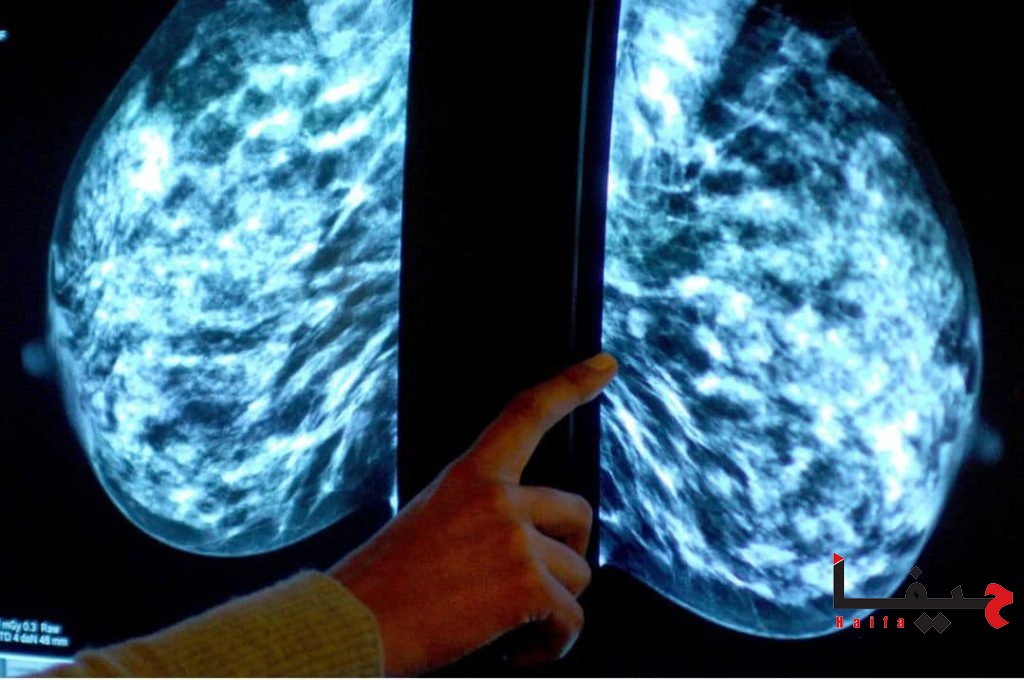

تمكن العالم، البروفيسور سعيد عمل أن يطوّر أداة آلية ثورية للذكاء الاصطناعي، يمكن بواسطتها تشخيص سرطان الثدي بدقّة تقارب 100٪. ويعتبر هذا إنجازًا علميًا غير مسبوق في مكافحة سرطان الثدي، بفضل العقول المبتكرة في جامعة نورث إيسترن في الولايات المتحدة.

واستطاع بروفيسور سعيد عمل وفريق مختبره للطب الدقيق، أن يطور أداة آلية ثورية، تتميز بدقة تشخيص مذهلة، تصل إلى 99.72% في الكشف عن سرطان الثدي. وقد قدم مع فريقه مؤخرًا كشفًا عن الاختراع إلى مركز الابتكار البحثي حول الفكرة.

ويمضي بروفسور عمل يقول: “سيتعلم الذكاء الاصطناعي من صورة عيّنة أنسجة الثدي عالية الدقة، ومن البيانات السابقة، كيفية تحديد أنماط السرطان، وإجراء التشخيص ودرجة انتشاره”. وأنه “لا يمكن للذكاء الاصطناعي أن يغفل وجود ورم في الخزعة ولن يتعب بعد تشخيص 10 أو 20 خزعة”. “كما أنه بالإضافة إلى دقة كهذه في التشخيص، سوف تتجنب المرأة جراحة غير ضرورية، وبهذا تتحسن حياة المريضة”.

وقام فريق الباحثين ببناء نموذج ذكاء اصطناعي عميق، يستخدِم عدة نماذج تم تدريبها على بيانات صورة أنسجة الثدي لزيادة الدقة وتقليل الخطأ.